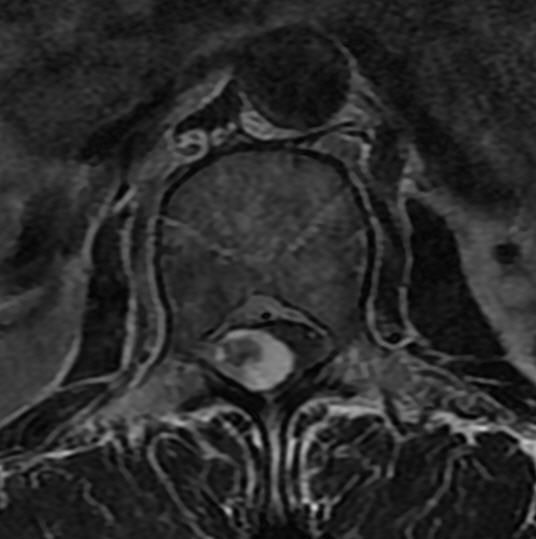

CT

-

CT可清楚地显示椎管横断面的骨性结构,对侧隐窝狭窄,黄韧带肥厚,椎间小关节病变及神经孔周围极外型椎间盘突出的显示有独特的临床价值,CT可提出比椎管造影更准确的鉴别诊断。CT对蛛网膜下腔观察不如脊髓造影。